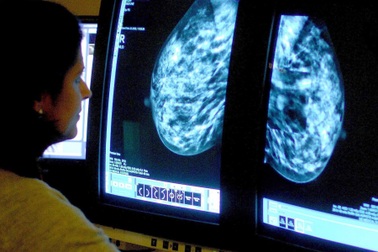

Phân biệt u vú lành tính và ung thư vúViệc phân biệt bệnh ung thư vú và u vú lành tính khá khó khăn đối với những người không có kiến thức về y khoa do 2 bệnh này có nhiều triệu chứng tương tự nhau.

Phân biệt khối u vú lành tính và ác tính như thế nào?U lành tính và u ác tính có một số điểm khác biệt. Tuy nhiên, để có kết quả chính xác, vẫn cần đến bệnh viện để bác sĩ khám, làm một số xét nghiệm, chiếu chụp.

Sờ thấy u ở vú, làm sao để biết ung thư hay u lành tính?Rất nhiều chị em sờ thấy u cục ở ngực lo lắng đến mất ăn mất ngủ vì sợ ung thư. Khi phát hiện u cục, đừng ngần ngại đến viện, bác sĩ sẽ có chỉ định phù hợp để xác định u vú lành tính hay ác tính.